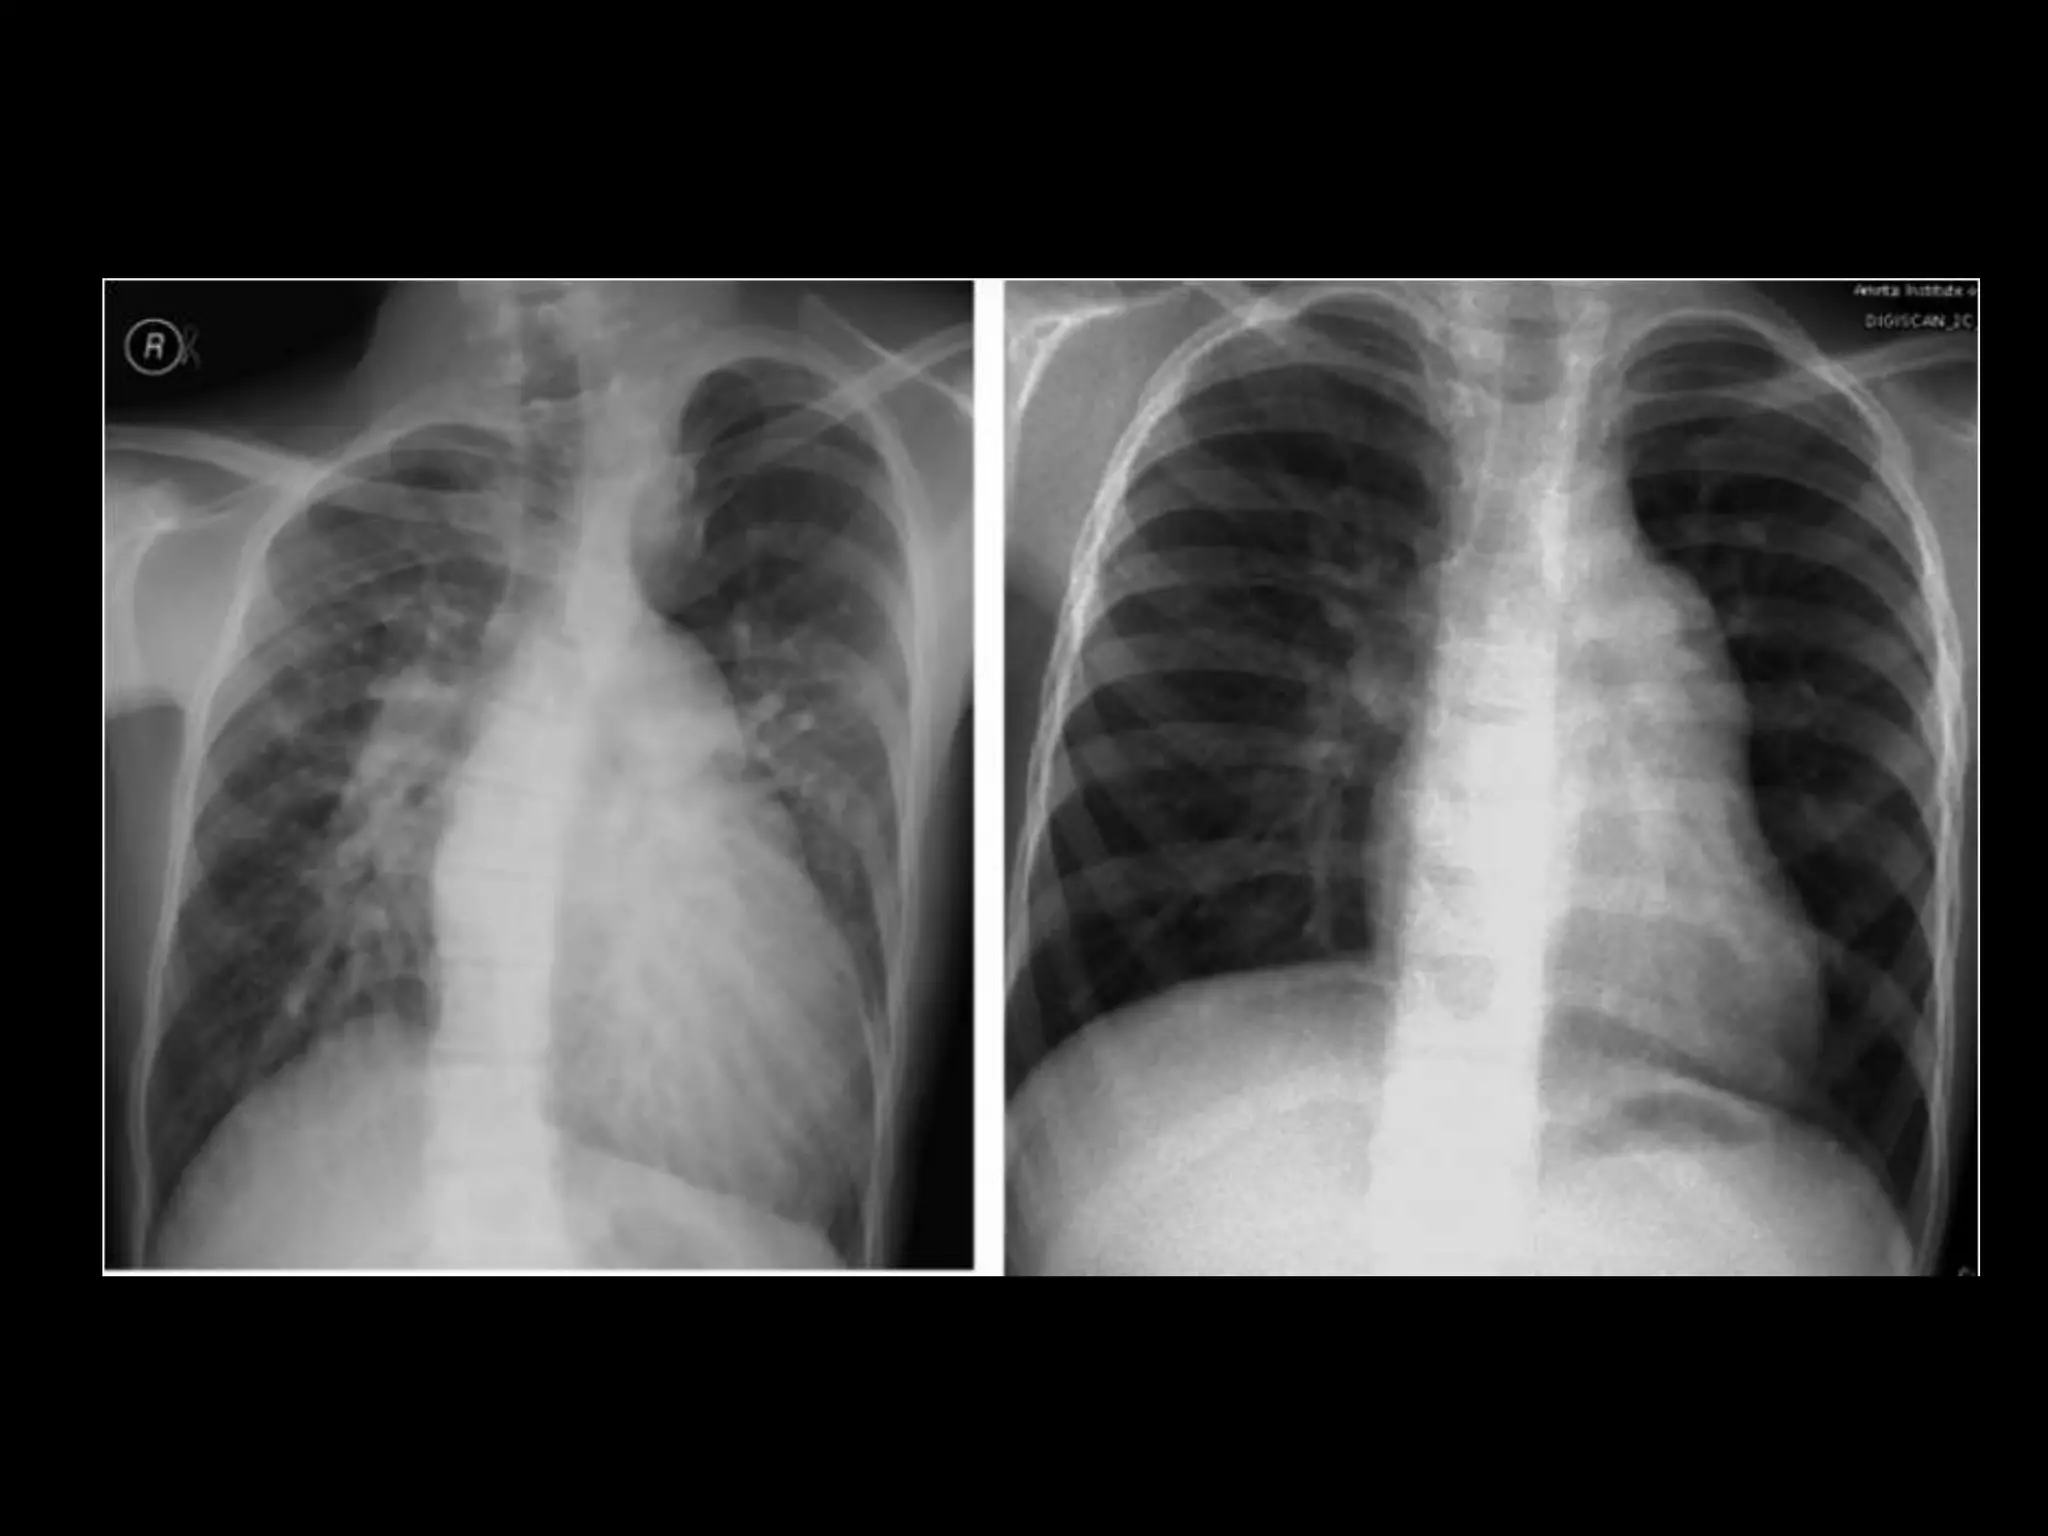

• Clinical evaluation

• Chest X-ray and ECG

CLINICAL ASSESSMENT • Serialassessment by multiple experienced clinicians improves the reliability of clinical examination as a tool in determining operability • The presence of ‘clinical cyanosis’ or saturations <90% is a strong predictor of inoperability whereas the clear detection of a MDM on serial assessment strongly favours operability.